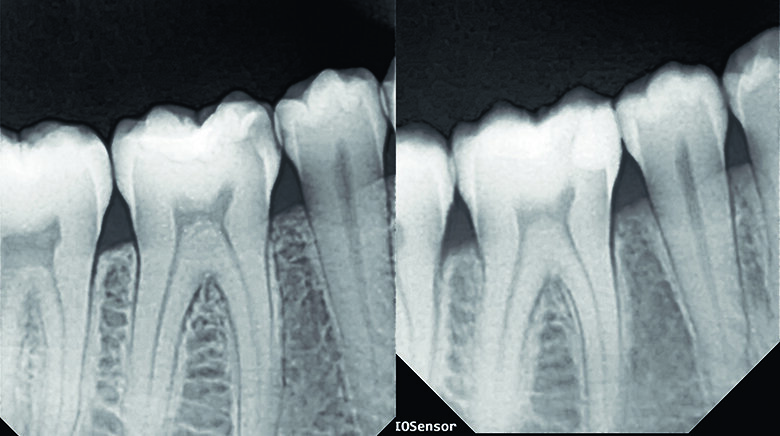

Caries removal was completed with a blue stripped high speed small round bur followed by slow speed round carbide bur. Caries detection dye was applied to ensure complete removal of active decay. Old composite was removed from occlusal and buccal pit area of tooth #46. For tooth #45, decay was initially removed without touching the occlusal surface, however as the marginal ridge area was left with very thin structure, the proximal box was later extended to the occlusal surface (C-shaped preparation) to avoid excessive stress that could lead to restoration failure (Fig. 2).

Fig. 2. Pre-wedging with removal of active decay on teeth #45, 46.

Fig. 12. IOPA before treatment and post-op showing natural contour and seal achieved with a perfect contact.